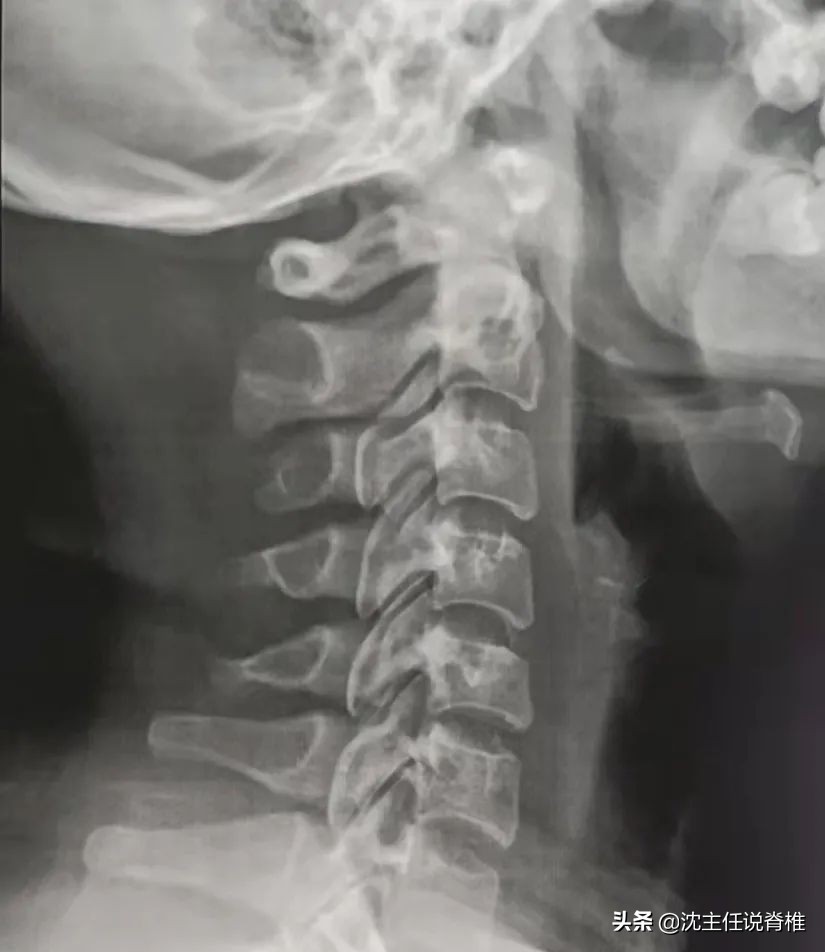

病人当时的颈椎拍片↑

对此导入一则颈椎曲度变直的病人通过一年的努力下, 恢复成正常曲度的“成功案例” !

病人当天马上预约了专业医生进行检查,并接受专业的手法治疗。经过一个星期三次的治疗后,耳鸣症状才逐渐消失。也是在这一次治疗中,病人才“因祸得福”知道了自己的颈椎曲度已经变直!

经过了一年时间,近日这位病人重新去拍了一组颈椎X光片,我们得到了她很好的反馈: 重获了一条非常“漂亮”的颈曲曲线!